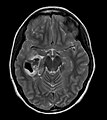

| Site | brain - typical temporal lobe |

- Classically in the temporal lobe in children and young adults.

- Temporal lobe - classic.

- Usually assoc. with the leptomeninges,[1] i.e. superficial (in up 96%).